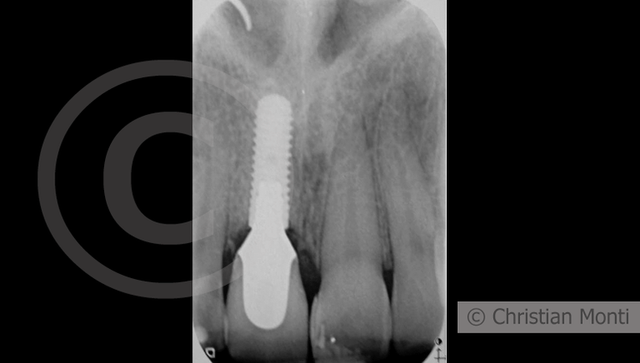

EDENTULIA SINGOLA

Impianto in sostituzione di un incisivo superiore